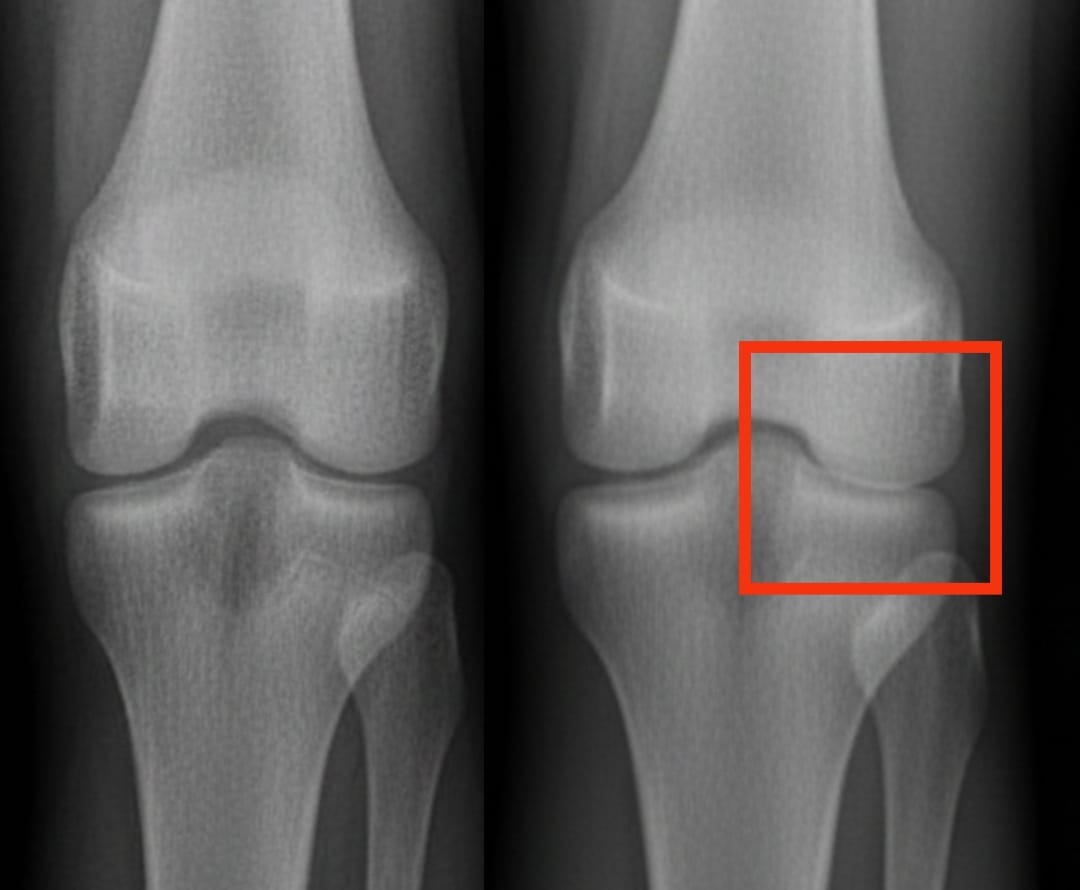

Il plasma ricco di piastrine alleva meglio l’artrosi del ginocchio rispetto ad altri trattamenti iniettabili?

L’artrosi del ginocchio colpisce centinaia di milioni di persone in tutto il mondo. È caratterizzata da un’usura progressiva della cartilagine, che provoca dolore e difficoltà nei movimenti. Tra le soluzioni proposte, le iniezioni di plasma ricco di piastrine suscitano un interesse sempre maggiore. Questo trattamento utilizza il sangue del paziente stesso, concentrato in piastrine, per stimolare la riparazione dei tessuti e ridurre l’infiammazione.